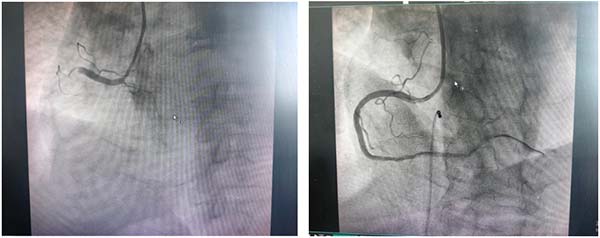

国庆假期的这个夜晚,对于听班医生——心内科汤克虎主任医师及科室同事而言,是一个与时间赛跑、与病魔抗争的不眠之夜。急性胸痛患者接连而至,病情就是命令!汤克虎凭借丰富的临床经验和精湛的技术,带领介入团队,通宵达旦,连续奋战,成功为四位急性冠脉综合征患者实施了急诊冠脉介入手术。

成功为其中一位下壁心肌梗死患者行介入治疗

每一台手术,都是对生命的郑重托付;每一刻坚守,都闪耀着医者仁心的光辉。从深夜到黎明,导管室内灯火通明,医护人员们全神贯注,精准操作,成功开通堵塞的血管,恢复了心肌的血液供应,将患者从死亡边缘拉回。他们忘记了疲惫,忽略了时间,心中唯一的信念就是尽快解除患者的病痛,守护每一颗跳动的心脏。